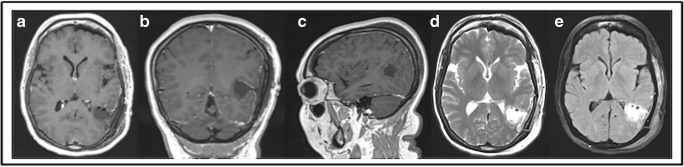

The patient experienced mild dysphasia postoperatively (naming difficulties, mainly in English) that recovered to her baseline after 2 weeks. The postoperative MRI documented completed resection (Fig. 4).

Fig. 4.

Postoperative MRI. Complete resection (gross total resection). a Axial T1 GAD. b Coronal T1 GAD. c Sagittal T1 GAD. d Axial T2. e Axial FLAIR